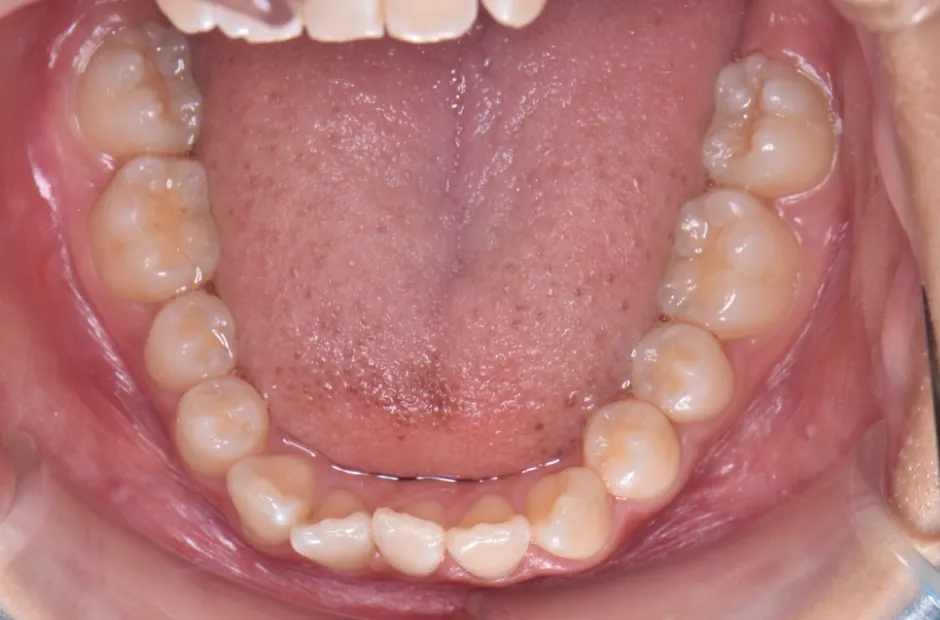

叢生

| 診断名・主訴 | 叢生 |

|---|---|

| 年齢・性別 | 10歳・女性 |

| 治療期間・回数 | 2年半 |

| 治療に用いた主な装置 | 拡大床装置 |

| 抜歯部位 | なし |

| 治療費 | 30万円(税抜) |

| リスク・副作用 | 装置による違和感・疼痛・歯肉退縮・歯根吸収・虫歯のリスクなど |

治療前

治療中

治療後